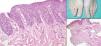

El análisis histopatológico permitió realizar un diagnóstico preciso de la alteración ungueal en 13 casos. En 4 casos el estudio histopatológico tanto de la lámina ungueal como del lecho demostró la presencia de estructuras fúngicas, siendo diagnosticados de onicomicosis (fig. 4). El diagnóstico de psoriasis se estableció en 5 casos (fig. 5), en 2 de ellos tras el estudio del lecho ungueal y en el resto tras realizar una biopsia de la matriz. El diagnóstico de melanoma se confirmó en un caso al presentar en la biopsia del lecho ungueal una proliferación de melanocitos neoplásicos agrupados en nidos irregulares en dermis papilar y reticular (fig. 6). Un caso fue diagnosticado de hematoma subungueal. Los dos pacientes a los que se les realizó una biopsia longitudinal lateral fueron diagnosticados de melanoniquia longitudinal (fig. 7), descartando la presencia de neoplasia. En dos casos la biopsia resultó inespecífica.